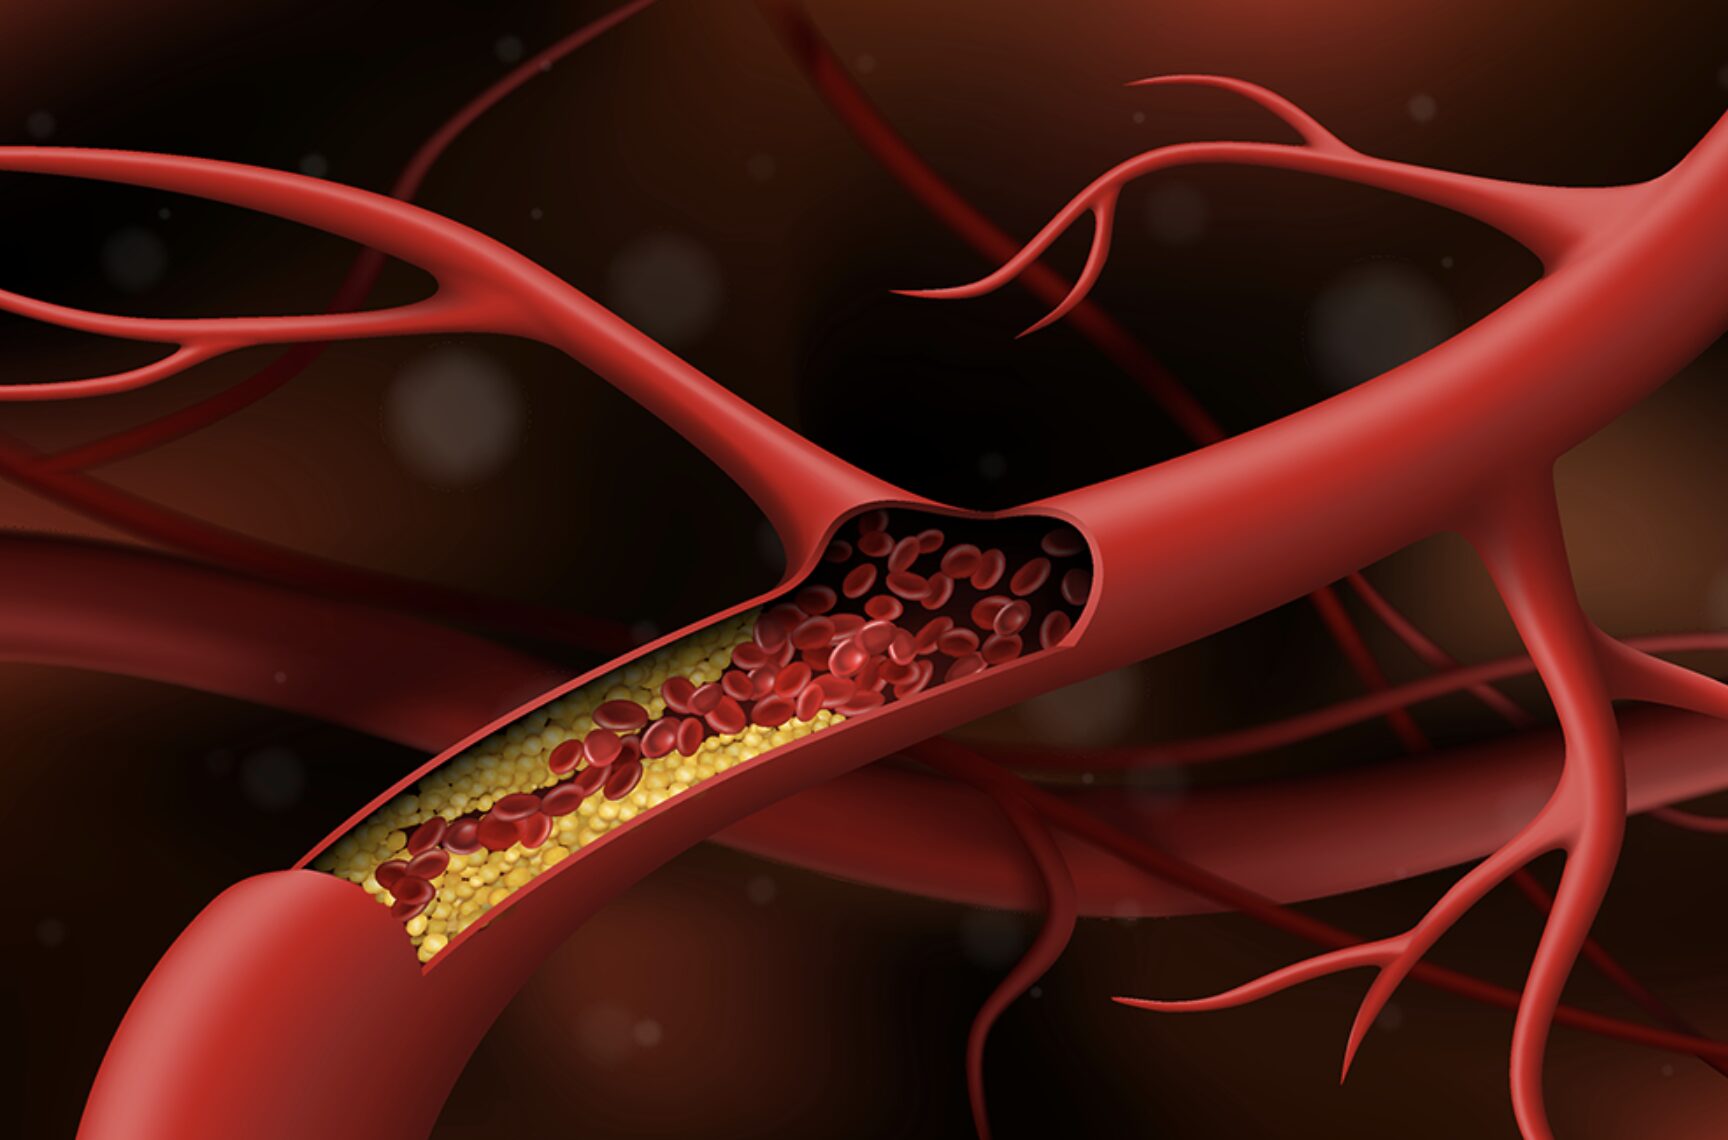

Tỷ lệ đột quỵ não tái phát trong 5 năm đầu tiên là 25%. Điều đó có nghĩa là cứ 100 bệnh nhân sống sót sau đột quỵ não, sẽ có 25 trường hợp bị tái phát. Vậy làm thế nào để những bệnh nhân mắc đột quỵ não sau khi ra viện có thế ngăn ngừa sự tái phát của bệnh?

Làm giảm nguy cơ tái phát đột quỵ não bằng cách nào?

Có nhiều cách làm giảm nguy cơ tái phát đột quỵ não. Trong đó, quan trọng nhất là kiểm soát tốt các yếu tố nguy cơ và thay đổi lối sống. Các yếu tố nguy cơ quan trọng nhất của đột quỵ não có thể thay đổi là tăng huyết áp, bệnh tim, tiểu đường, hút thuốc lá, v.v…

Tái phát sau đột quỵ não

Tỷ lệ đột quỵ não tái phát trong 5 năm đầu tiên là 25%, nghĩa là cứ 100 bệnh nhân sống sót sau đột quỵ não, sẽ có 25 trường hợp bị tái phát. Để làm giảm mức độ tái phát đột quỵ, người bệnh cần uống thuốc đúng theo chỉ định của bác sĩ và đi tái khám đều đặn.